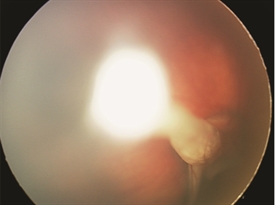

Figure 2.

The most important disease to rule out when a child presents with leukocoria is retinoblastoma (a rare malignant tumor of the retina). Typically, if one is able to visualize the back of the eye, a stalk is seen spanning the space between the optic nerve and the back of the lens (Figure 2). If the view into the back part of the eye is challenging, ultrasound and/or CT/MRI scans are often performed.